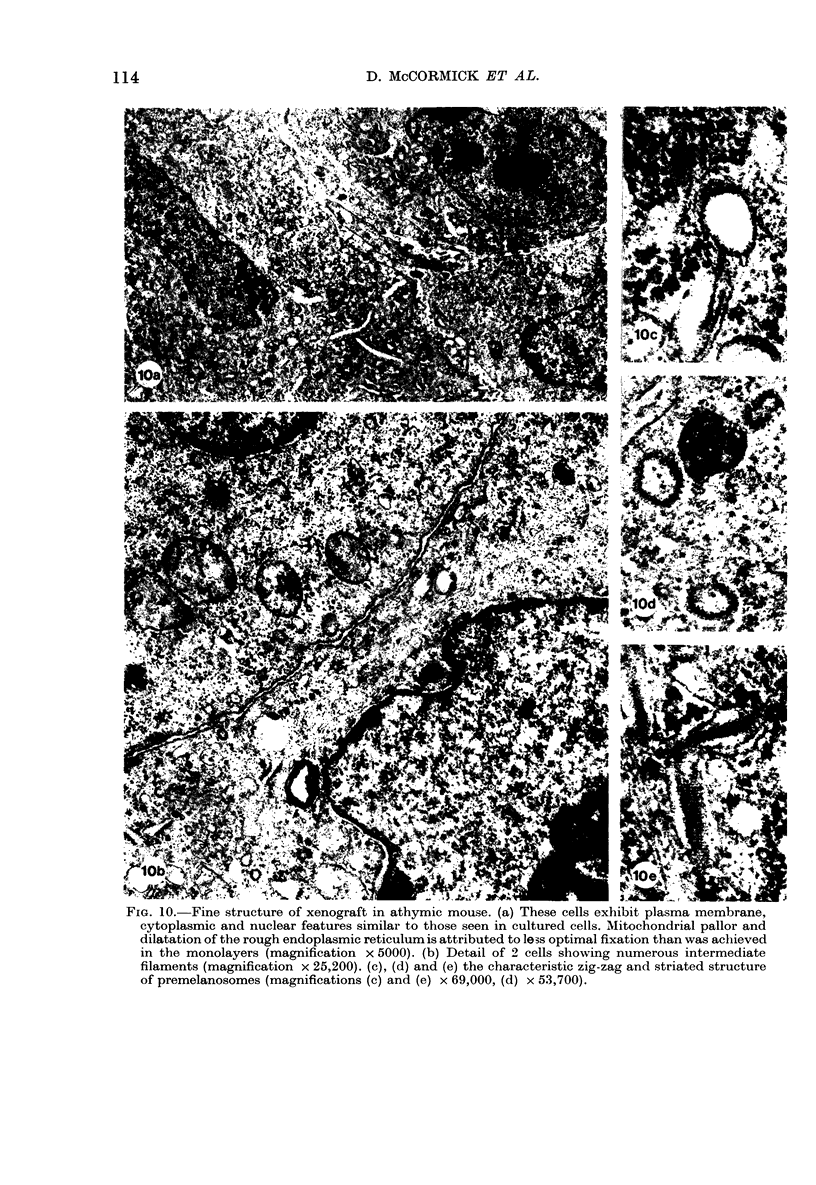

A permanent cell line has been established from a human intracranial secondary melanoma. During 3 years of continuous growth in vitro the cells have maintained their characteristic phenotypic properties including melanin production. The cultured cells are highly tumorigenic in the athymic mouse and the tumours produced are histologically identical to the human tumour of origin.